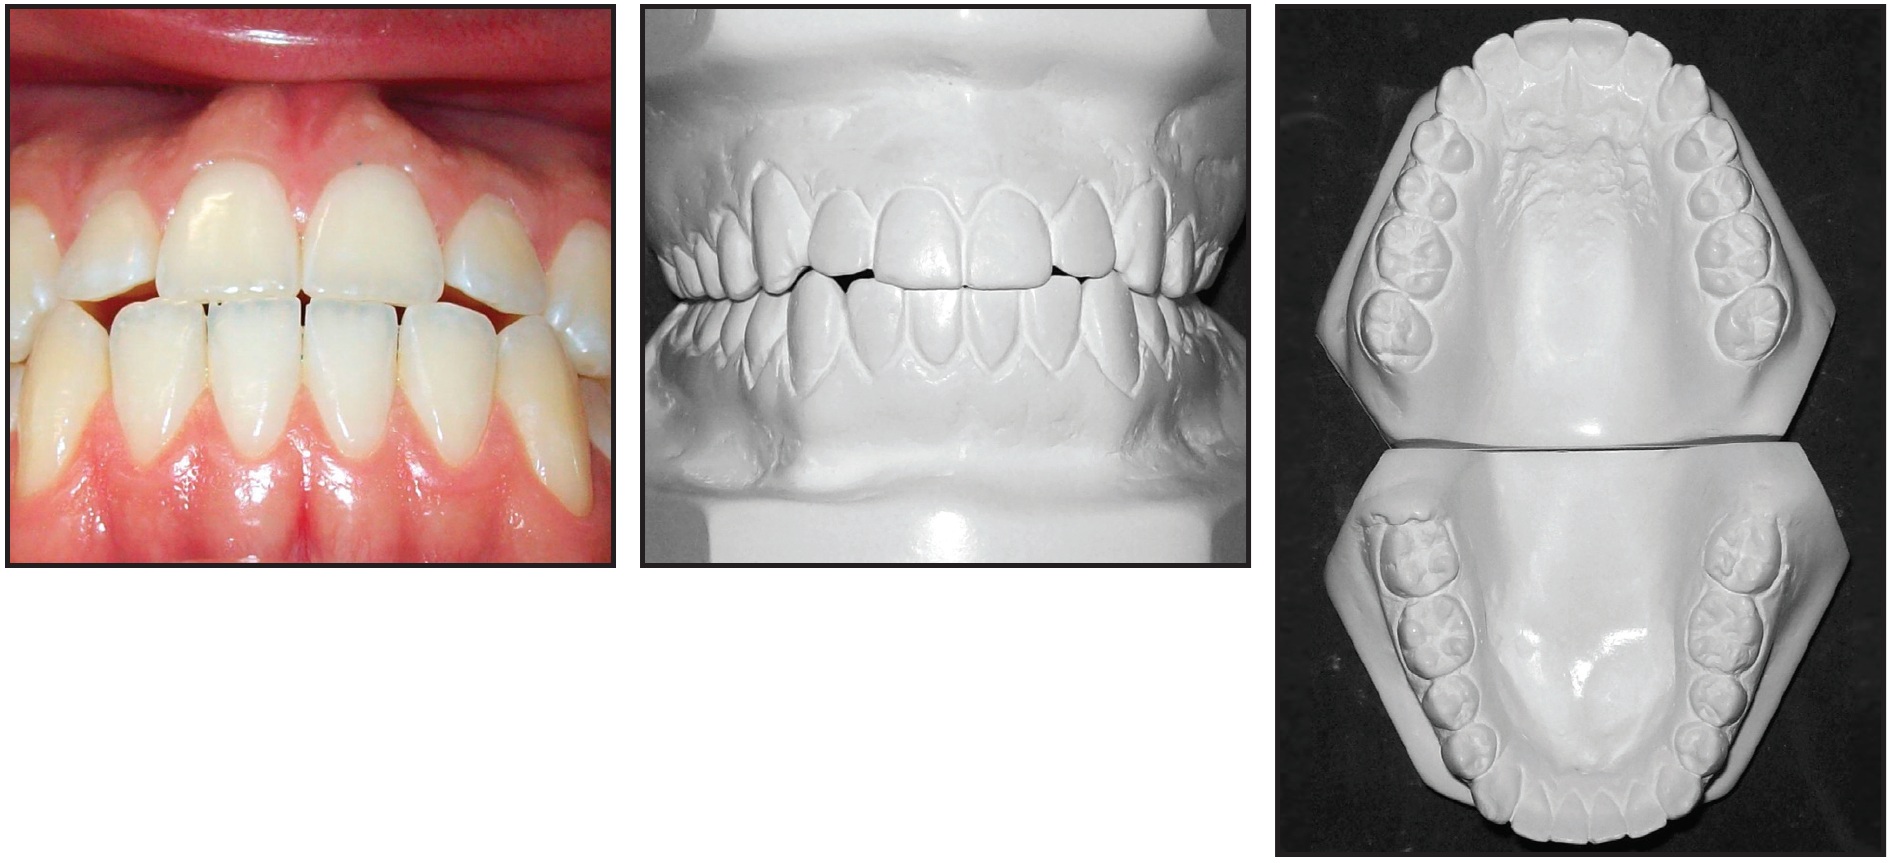

Fig. 1 21-year-old male patient with mild Class III malocclusion, minor crowding, long lower face, and mandibular macrognathism before treatment (continued on next image).

Fig. 1 (cont.) 21-year-old male patient with mild Class III malocclusion, minor crowding, long lower face, and mandibular macrognathism before treatment.

The patient had a straight profile with excessive lower facial height, a dental Class III malocclusion, minor crowding in both arches, edge-to-edge incisor relationships, and slightly proclined upper and lower incisors. Radiographic analysis indicated a mild skeletal Class III pattern and mandibular macrognathism. The panoramic radiograph showed adequate root integrity and anatomical symmetry.